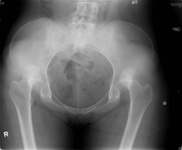

Radiografia mostrando luxação posterior bilateral do quadril

Fan KY, et al. BMJ Case Rep. 2015 Mar 25:2015:bcr2014204031; usado com permissão